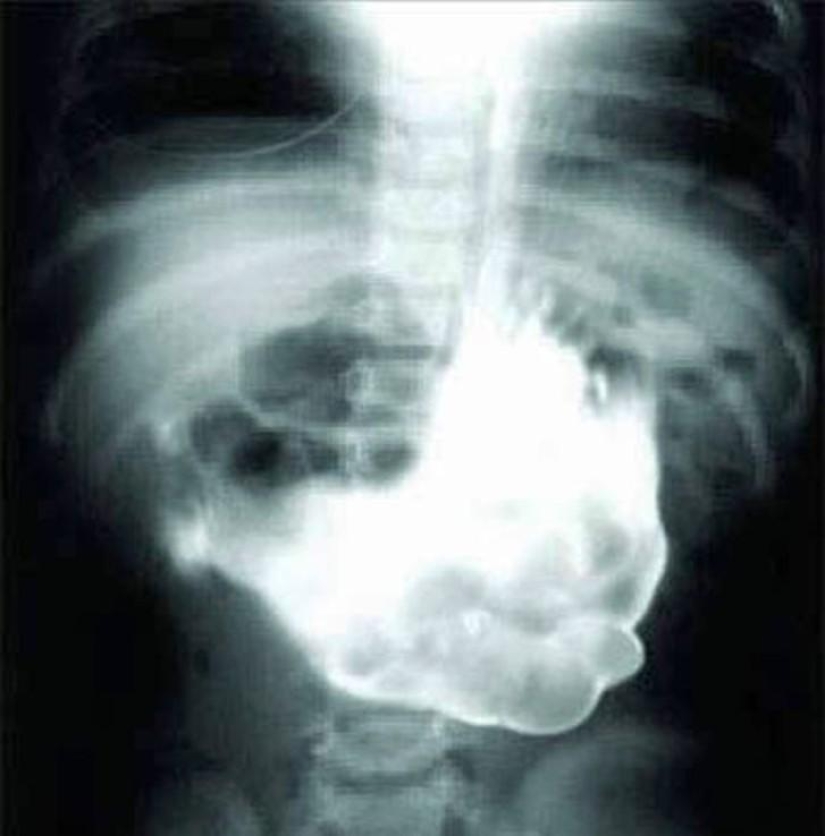

10. The nail.